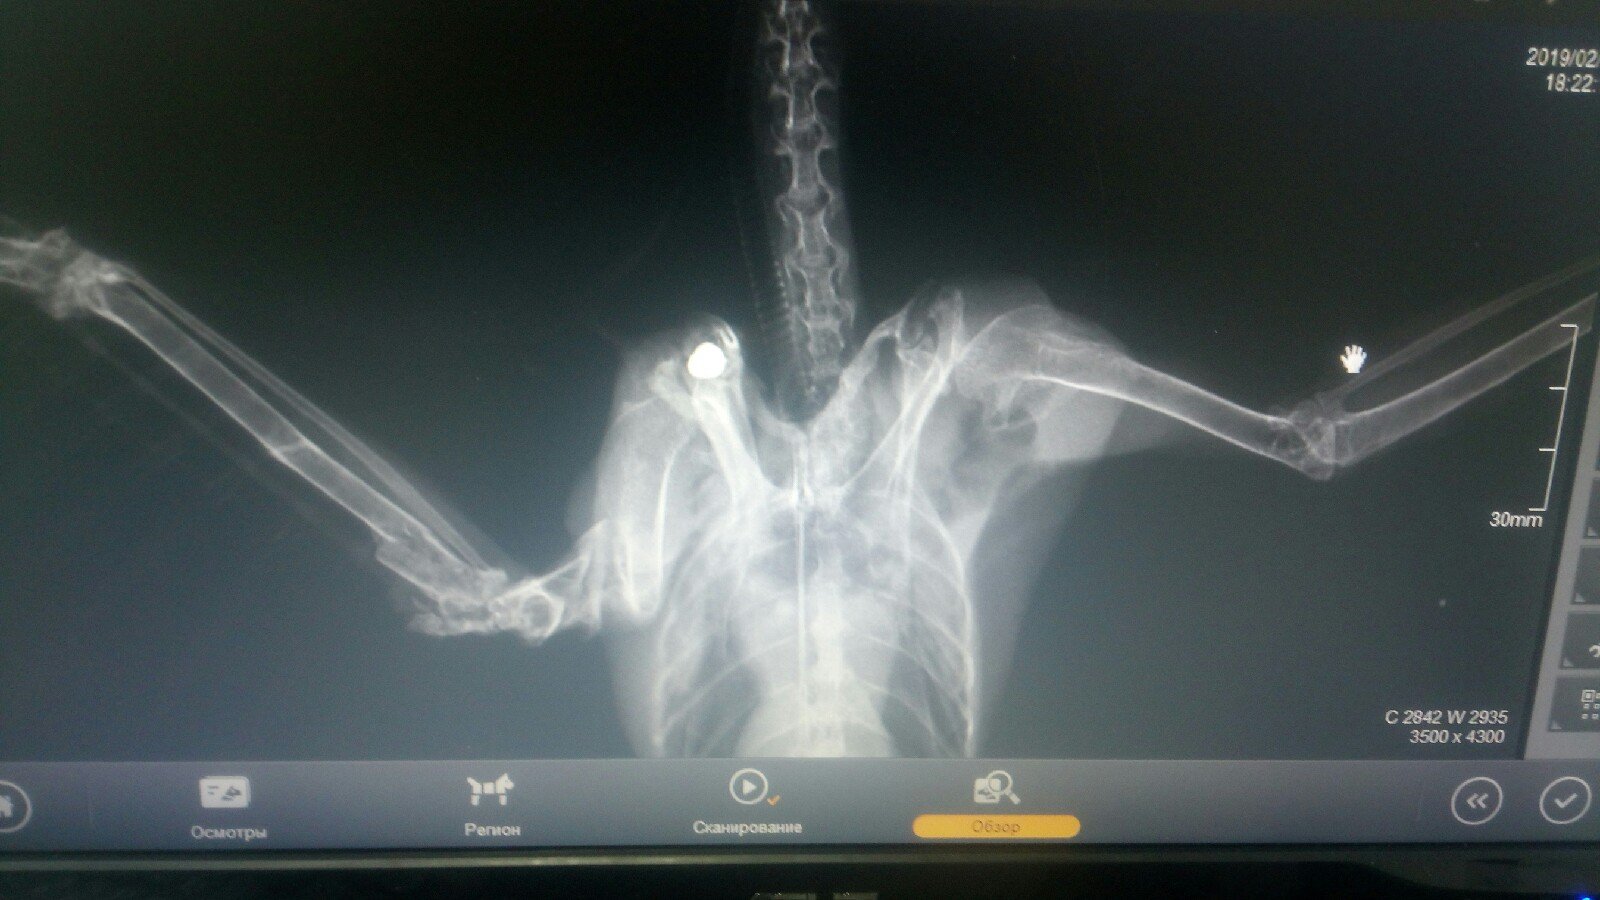

Вышел перед ночью из дома, на ступеньке сидел(а) ворона, очень крупная с висящим крылом, на следующий день сделал рентген. Единственный орнитолог, к кому отправляют все до понедельника не может, и то только вечером. Хотелось бы знать какие действия предпринять в этой ситуации, т.к. ему ещё 2 дня сидеть почти.... Из того что я понял со снимка, пуля сидит в спине, и в суставе крыла осколок пули тоже есть. Заведомо извиняюсь если что не так оформил, т.к. очень устал и немного паникую из-за животного